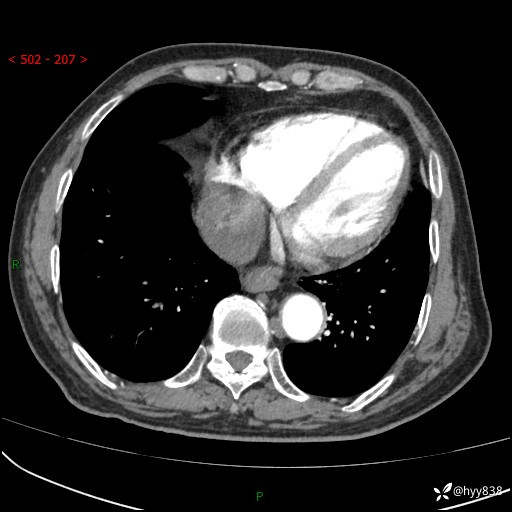

老年男性,检查发现心脏肿物1周余。少见病例,请讨论---结果公布~

主诉:检查发现心脏肿物1周余。

现病史:患者一周余前因腹胀就诊我院消化科门诊,查心脏彩超提示右房内异常回声(粘液瘤?),无明显心慌、气喘、胸闷,无明显胸痛、咳嗽咳痰等不适,活动量增加后出现心慌、气喘不适。现为求进一步治疗,就诊我科,门诊遂以“心脏肿物”收入院。 自发病以来,精神睡眠一般,食欲尚可,大小便正常,体力下降,体重无明显变化。

胸部CT平扫+增强